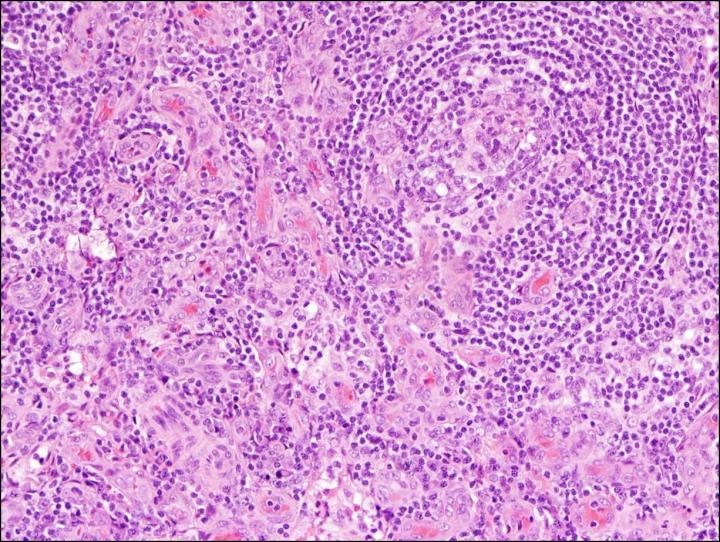

To establish the criteria, the international working group - led by Fajgenbaum and consisting of 34 pediatric and adult hematopathology, hematology/oncology, rheumatology, immunology, and infectious diseases experts in iMCD and related disorders representing eight countries on five continents, including two physicians that are also iMCD patients - reviewed 244 iMCD cases and 88 lymph node tissue biopsies over 15 months.